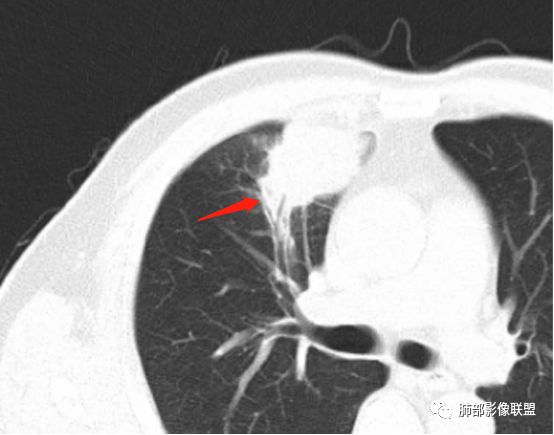

支气管进入病灶内,近端堵塞,断端圆钝。

支气管壁均匀稍增厚。

甄德强:圆钝是良性病变特点吧。鼠尾是恶性特点。南边:层厚太厚了一点,我看不清这个低强化区边界,似乎较清晰。

小泡征,在良性病变中是罕见的,但需要除外小的坏死,除外炎性结节,支气管充气征,在良性病变中罕见,但炎性结节的支气管和肺癌,一般可以鉴别,我也提出了支气管边缘截断征的概念,来代替支气管截断征,在病变边缘将支气管截断的,高度提示肺癌。走到一半截断的,炎症,肺癌,均可;贯穿的,炎性多见。但肺癌也可见到,但支气管的管径一般会有狭窄或扩张(黄勇老师观点)。

张晴:@甄德强 庆安县人民医院 影像科?这个算边缘截断吗?甄德强:这个我支持支气管进入病灶内截断,(良恶性)一半一半。

就是黄老师说的炎症和肿瘤都可以。

德强:这个支气管是近端截断还是进入截断?

边缘截断更倾向于恶性。进入后截断良恶性都可以。

还是支气管进入后截断。

虽然本例患者支气管截断,病灶中央截断炎性及恶性都可以,断端向病灶一侧圆钝更支持炎性。